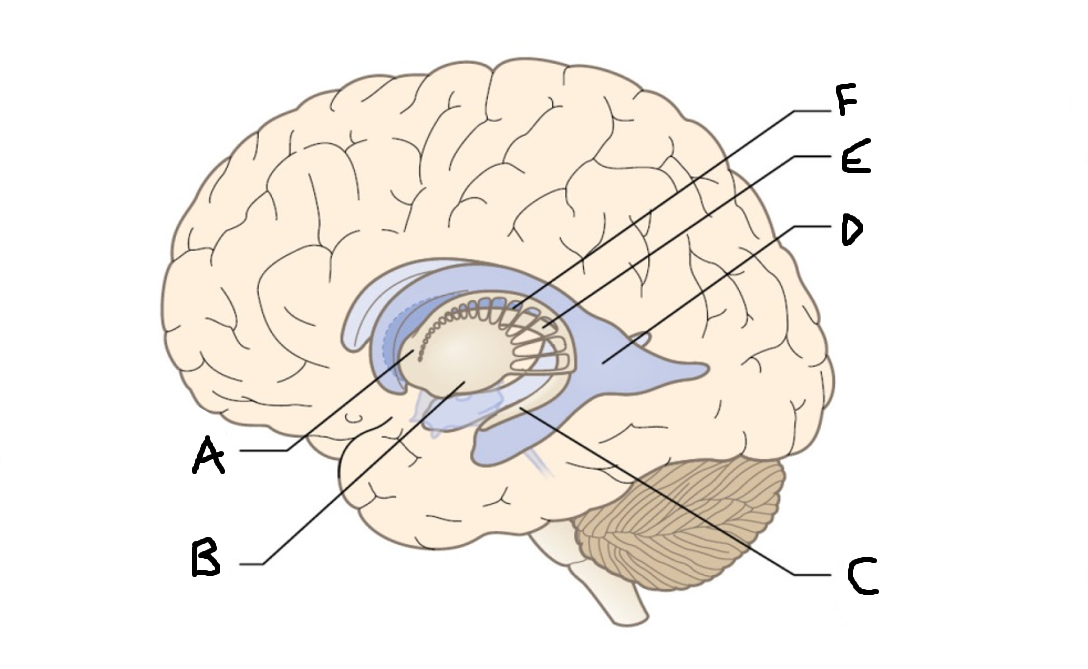

B

anterior horn of lateral ventricle

C

head of caudate nucleus

D

internal capsule (anterior limb)

E

putamen

F

globus pallidus

G

Thalamus

H

External capsule

I

internal capsule (posterior limb)

J

tail of caudate nucleus